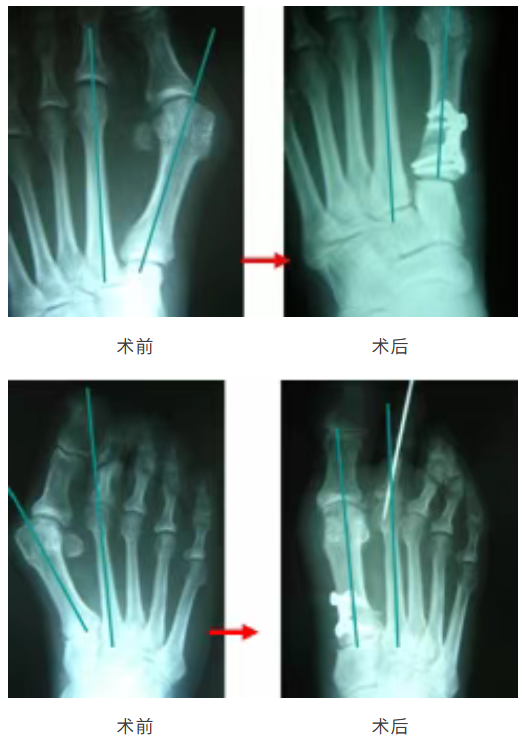

臨床應(yīng)用病例

楔形鎖定板

型號(hào):DGB07

楔形高度:0/2/3/4/5/6/7mm